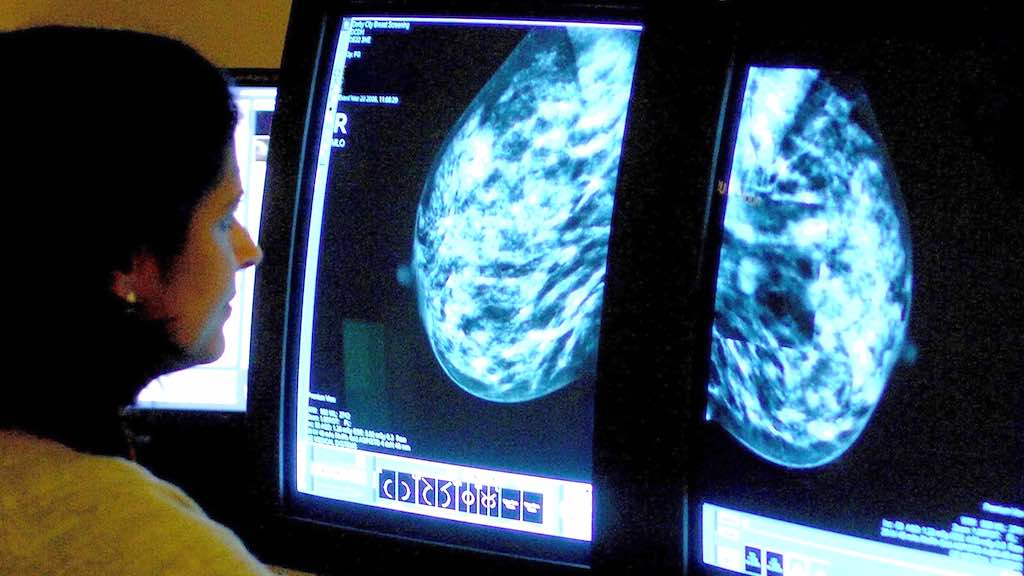

Um sistema de inteligência artificial do Google se mostrou eficaz – como um radiologista experiente – ao detectar que mulheres tinham câncer de mama com base em exames de mamografias, representando uma promessa de melhora na redução de erros, afirmaram pesquisadores nos Estados Unidos e Reino Unido.

A pesquisa, publicada na revista científica Nature na quarta-feira, 1, é a mais recente a mostrar que a tecnologia de inteligência artificial (IA) tem o potencial de melhorar a precisão nos exames de câncer de mama, que afeta uma em cada oito mulheres no mundo.

Radiologistas tendem a não detectar cerca de 20% dos casos de câncer de mama em mamografias, afirma a Sociedade Americana do Câncer, e metade de todas as mulheres que passam por exames no período de 10 anos recebem um resultado falso positivo.

As conclusões da pesquisa, desenvolvida com a unidade DeepMind AI, do Google, representam um grande avanço no potencial para a detecção precoce do câncer de mama, afirmou Mozziyar Etemadi, um dos co-autores da pesquisa e que trabalha na Northwestern Medicine em Chicago.

A equipe de pesquisadores, que inclui cientistas do Imperial College London e do Serviço Nacional de Saúde do Reino Unido, treinaram o sistema do Google para identificar câncer de mama em dezenas de milhares de mamografias.

Eles então compararam a performance do sistema com os diagnósticos dados aos exames, formados por um conjunto de 25.856 mamografias realizadas no Reino Unido e 3.097 realizadas nos Estados Unidos.

O estudo mostrou que o sistema de IA do Google conseguiu identificar casos de câncer com um grau similar de precisão atribuído a radiologistas experientes. O sistema conseguiu também reduzir o número de resultados falsos positivos em 5,7% no caso dos exames norte-americanos e em 1,2% no caso dos exames britânicos.

A tecnologia também reduziu o número de falsos negativos, que ocorrem quando os diagnósticos dos exames mostram, de forma errônea, um resultado considerado dentro da normalidade. A redução foi de 9,4% no caso do grupo de exames feitos nos EUA e em 2,7% no caso britânico.

As diferenças refletem as diferentes formas como as mamografias são lidas em ambos os países. Nos EUA, apenas um radiologista avalia os resultados e os testes são feitos a cada um ou dois anos. Na Inglaterra os exames são feitos a cada três anos e cada teste é lido por dois radiologistas. Quando eles não concordam entre si, um terceiro é chamado para avaliar o caso.